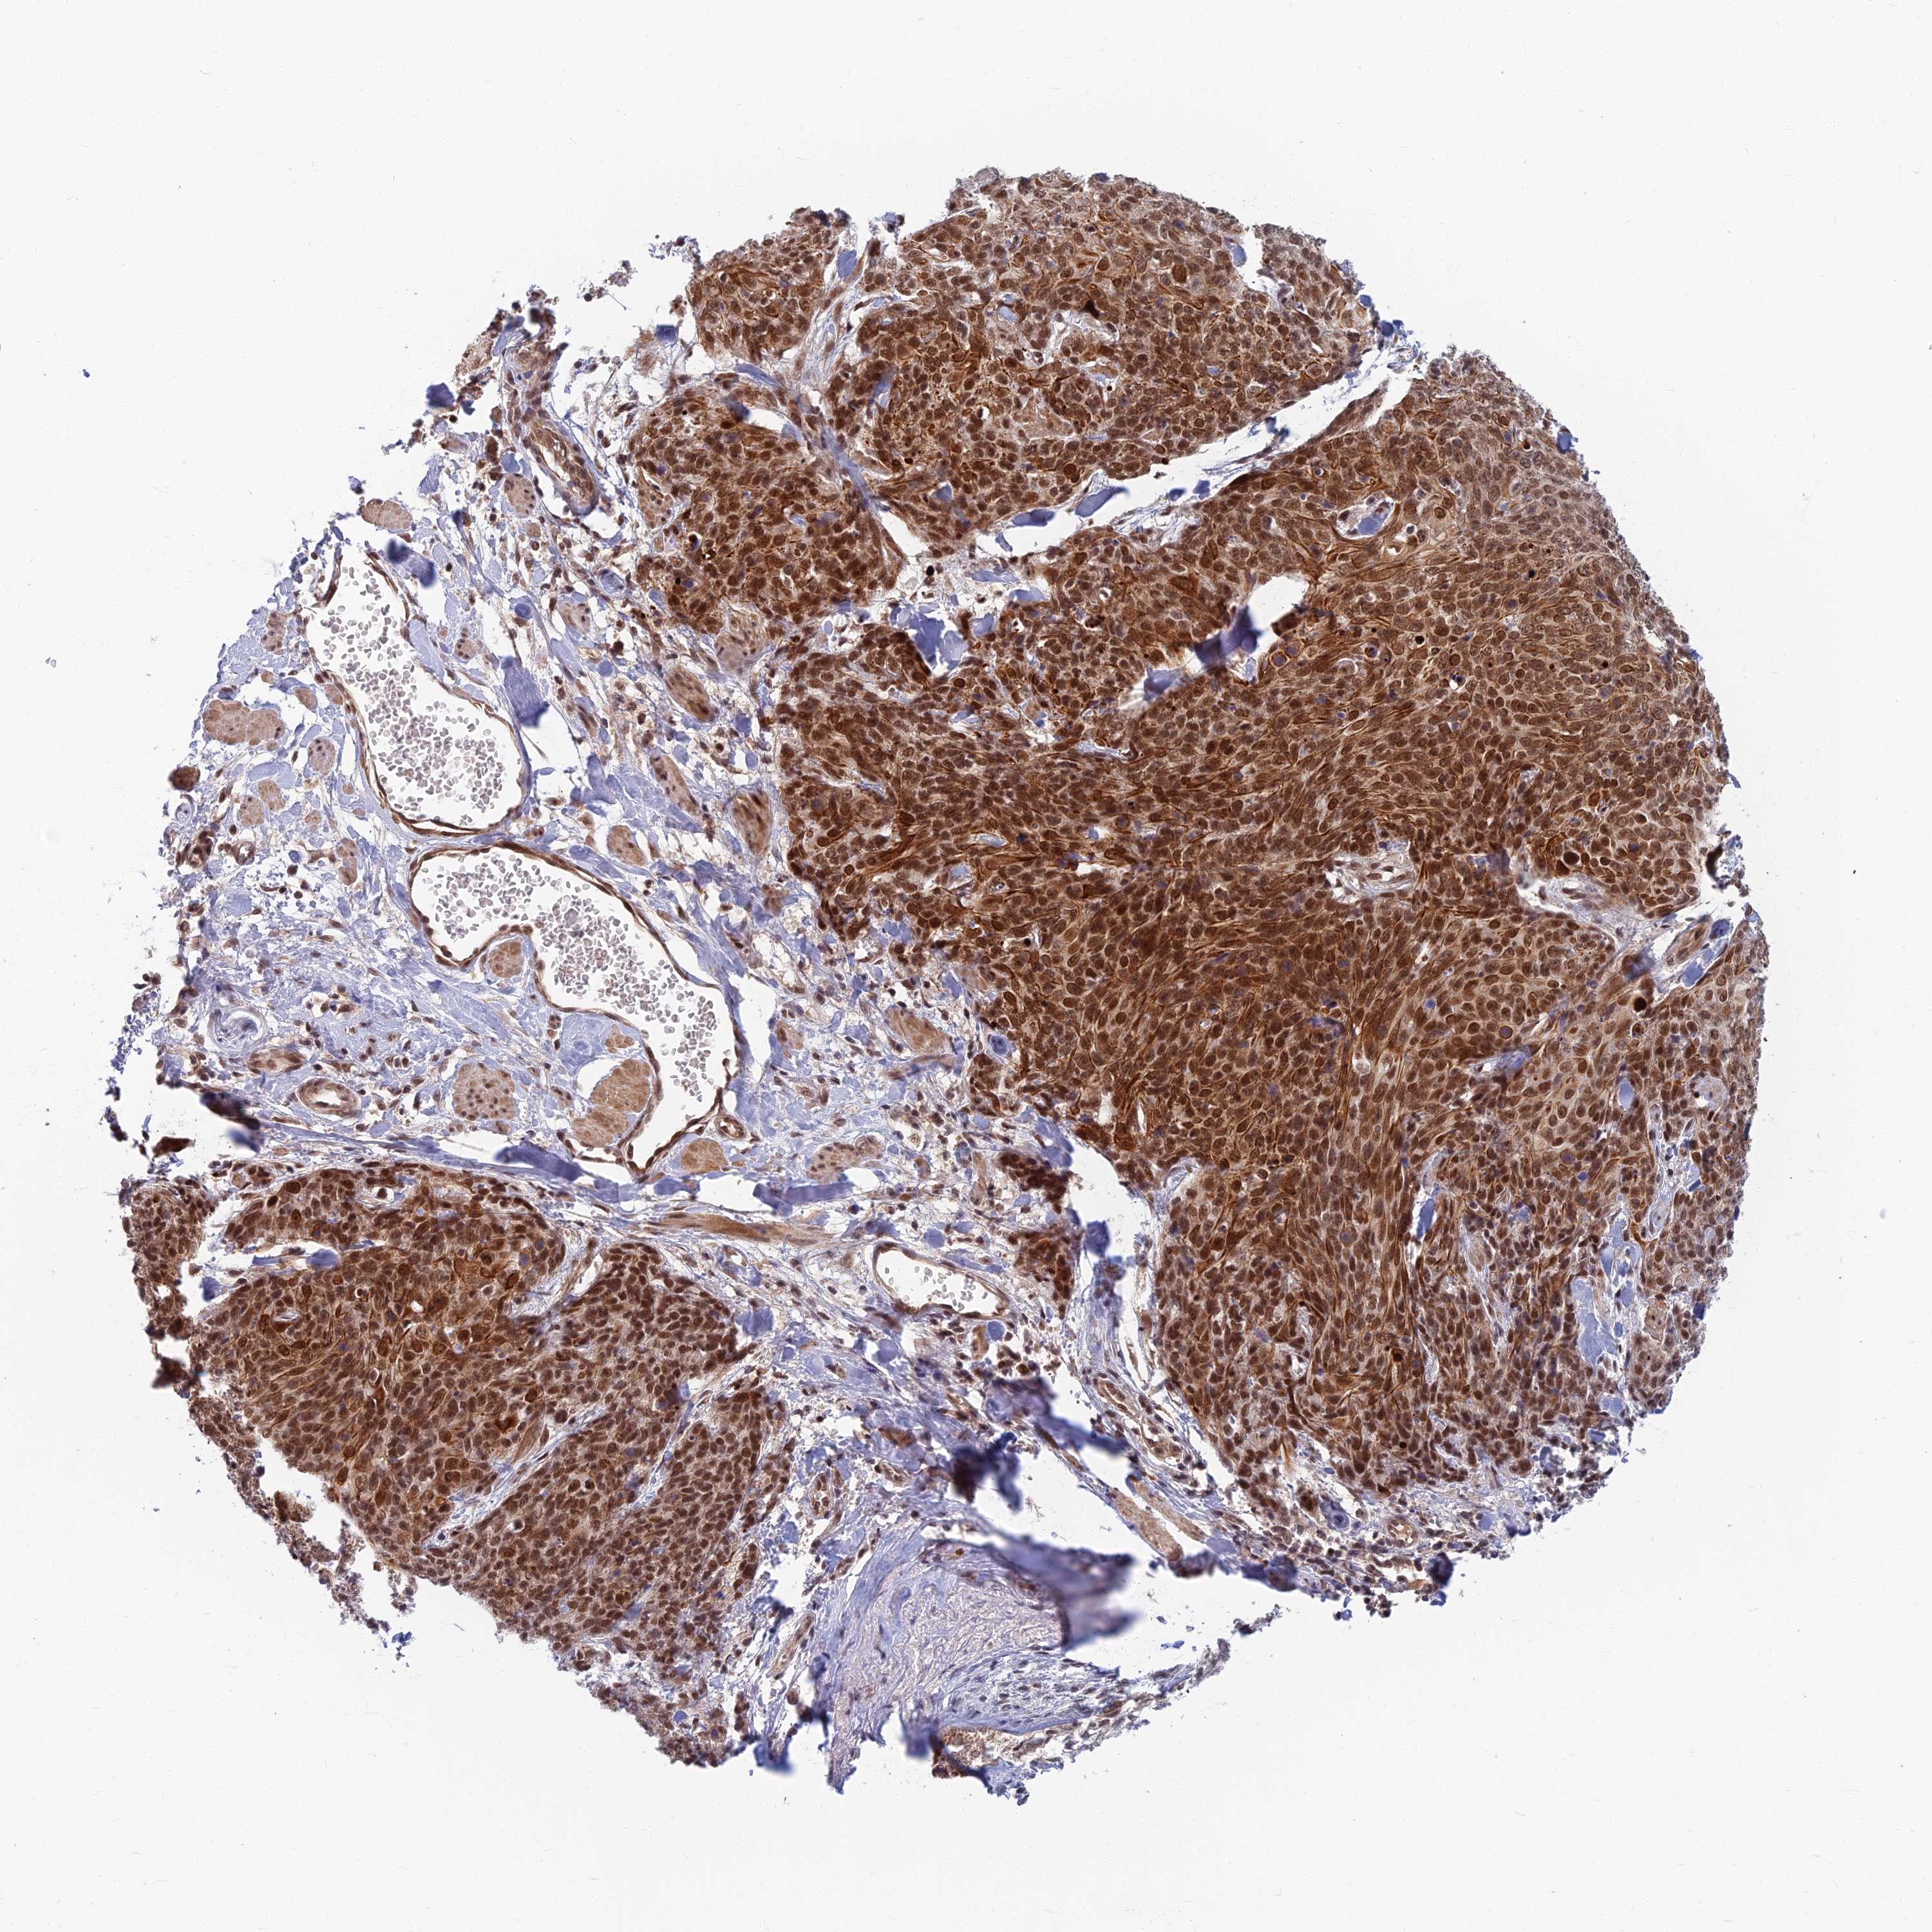

CANCER SKIN CANCER Show tissue menu

Basal cell and squamous cell cancer

SKIN CANCER - Protein expressioni

A mouse-over function shows sample information and annotation data. Click on an image to view it in a full screen mode. Samples can be filtered based on level of antibody staining by selecting one or several of the following categories: high, medium, low and not detected. The assay and annotation is described here.

Antibody stainingi

Antibody staining in the annotated cell types in the current human tissue is reported as not detected, low, medium, or high, based on conventional immunohistochemistry profiling in selected tissues. This score is based on the combination of the staining intensity and fraction of stained cells.

Each image is clickable and will lead to virtual microscopy that enables deeper exploration of all samples and also displays staining intensity scores, fraction scores and subcellular localization as well as patient and tissue information for each sample.

Antibody HPA043836

Staining

High

Intensity

Strong

Quantity

>75%

Location

Nuclear

Basal cell carcinoma

Squamous cell carcinoma, NOS

Squamous cell carcinoma, metastatic, NOS